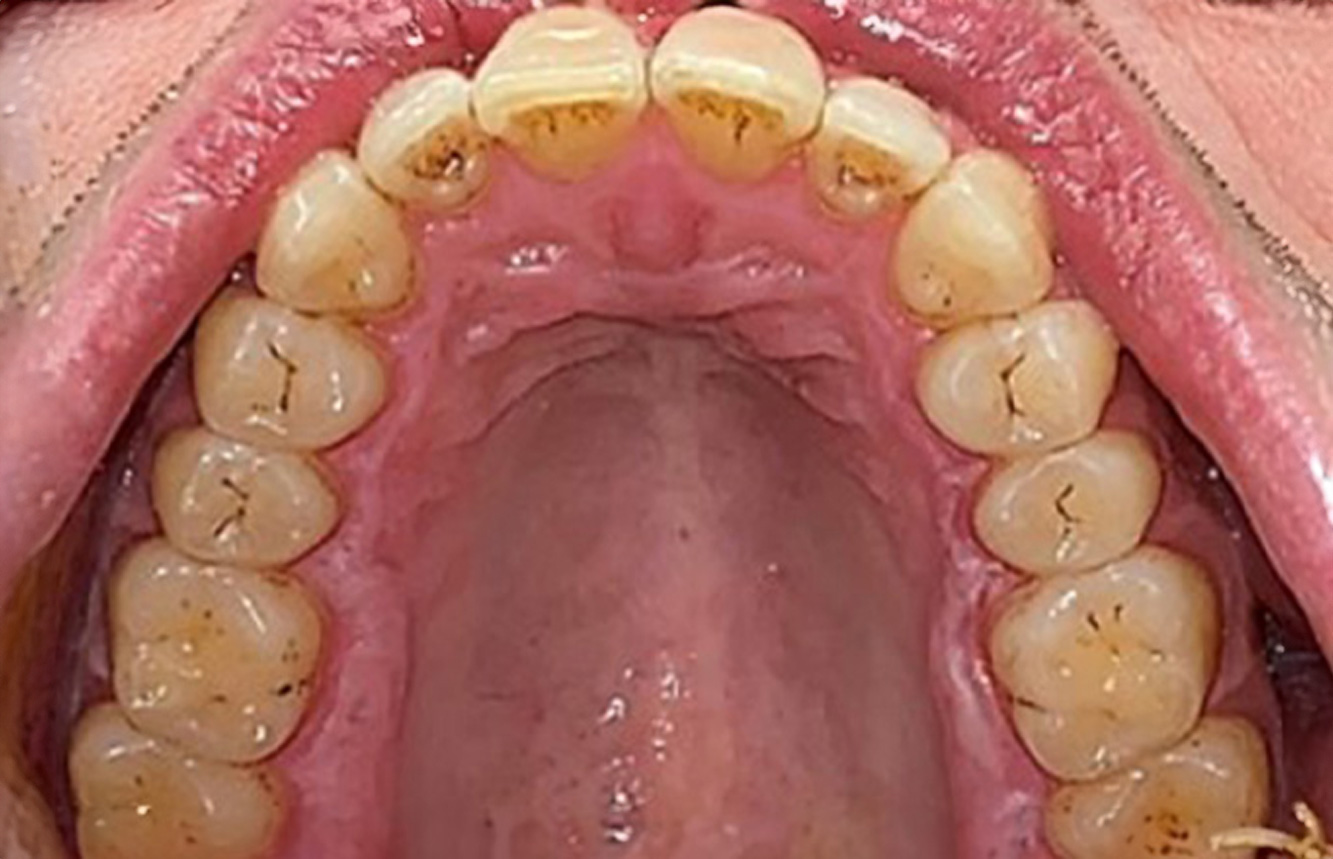

The 28-Year-Old Cigarette Smoker with Dental Erosions

28-year-old patient, smoker, with erosions. The bidirectional relationship between oral and general medical health is very well known. It is no longer sufficient – and arguably even old-fashioned – to consider intraoral conditions in isolation. In order to create a personalized, case-specific preventive and patient profile, it is essential to take a detailed medical history and perform diligent examination of the general medical and intraoral health, as well as considering the two in combination. more